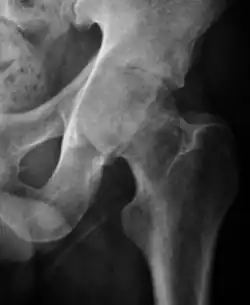

- Osteoarthritis

In adults, one of the main indications for radiographs is the detection of osteoarthritic changes (Figure 1(e)). Nevertheless, radiographs usually detect advanced osteoarthritis that can be graded according to the Tönnis classifications. The grading system ranges from 0 to 3, where 0 shows no sign of osteoarthritis. Intermediate grade 1 shows mild sclerosis of the head and acetabulum, slight joint space narrowing, and marginal osteophyte lipping. Grade 2 presents with small cysts in the femoral head or acetabulum, moderate joint space narrowing, and moderate loss of sphericity of the femoral head. Grade 3 is the severest form of osteoarthritis, which manifests as severe narrowing of the joint space, large subchondral cyst with productive bone changes that may lead to deformity of the bone components of the joint, while secondary osteoarthritis due to calcium pyrophosphate deposition can be diagnosed when calcification of hyaline cartilage and fibrocartilage is detected.[1]

There are other pathological conditions that can affect the hip joint and radiographs help to make the appropriate diagnosis. Acute bacterial septic arthritis can be diagnosed by radiographs when a fast regional osteoporosis and destructive monoarticular process develops (Figure 1(f)). In case of tuberculous or brucella arthritis it is manifested as a slow progressive process, and diagnosis may be delayed.[1]

Radiological signs of transient osteoporosis of the hip include localized osteoporosis of the femoral head and neck (Figure 8). Nevertheless, final diagnosis has to be made with MRI to differentiate it from avascular necrosis and from insufficiency or stress fractures of the femoral head or neck. In case of AVN, radiographs can only demonstrate delayed or advanced signs. Staging according to Ficat classification ranges between normal appearance (stage I), slight increased density in the femoral head (stage II), subchondral collapse of the femoral head with or without “crescent” sign (stage III), and advanced collapse with secondary osteoarthritis (stage IV). In the case of stress or insufficiency fractures X-ray sensitivity has been proven to be much lower than MRI, which is currently the gold standard.[1]